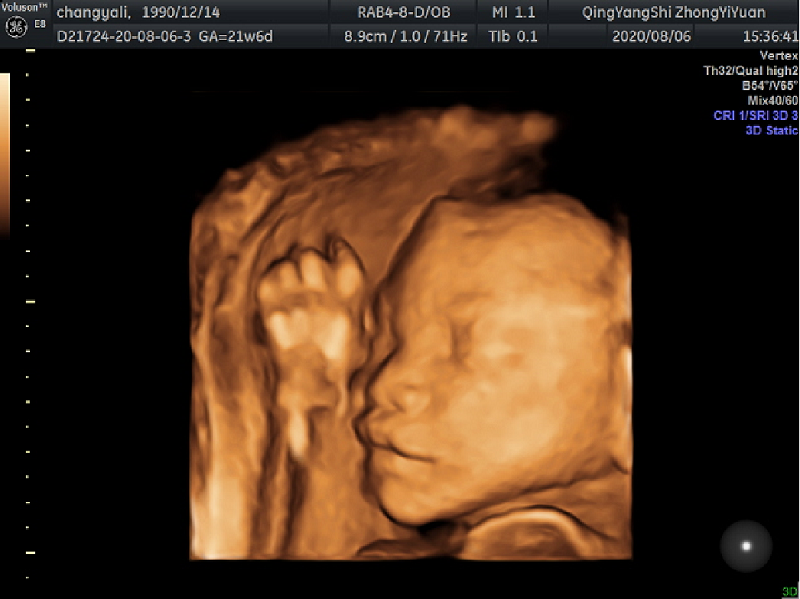

很多孕妈妈在进行孕期的检查时都需要做胎儿系统性超声筛查(胎儿四维),那么筛查什么时间做最适合?主要是查什么?到庆阳市中医医院来做检查又要注意些什么呢?带着诸多问题,我们一起去了解一下。

答:胎儿四维即胎儿系统性超声筛查,主要对胎儿颅脑、颜面部、胸腹部、心脏、四肢等器官系统的大体形态结构进行筛查,通过数十个标准切面来评估胎儿结构是否正常。

答:通常在孕22~24周进行,这期间胎儿的基本结构已经形成,胎儿大小和羊水量适中,在子宫内活动空间较大,形成的图像比较清晰,有利于医生查看。当然,每位孕妇的身体状况不同,做四维彩超的时间也会略有差异,建议做之前咨询医生,谨遵医嘱。